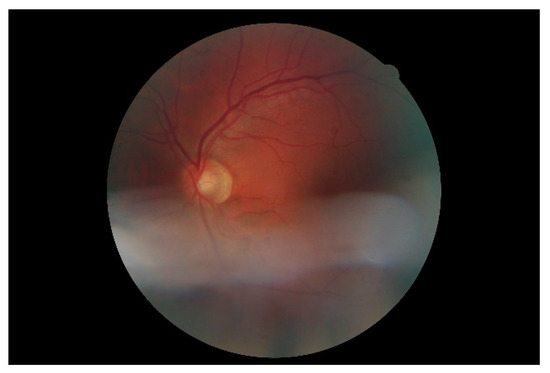

Figure 8. Retinal image (low quality).

Figure 7 shows a simple example of the MLP method used in this study. The high-resolution fundus (HRF) [74] image dataset contains higher-quality retinal images compared to those of DRIVE, and provides both low- and high-quality retinal images. Figure 8 shows a low-quality retinal image. The bottom part of the image is unclear owing to white noise caused by environmental factors. Figure 9 shows a retinal vessel image created by performing vessel segmentation on Figure 8. The white noise seen in Figure 8 also affects vessel segmentation. Figure 10 is a high-quality retinal image and the white noise observed in Figure 8 has disappeared. The bottom part of the vessel stem is clearly visible, which did not appear in the original image. Figure 11 shows a retinal vessel image created by performing vessel segmentation on Figure 10. Unlike Figure 9, the bottom part of the vessel stem is shown clearly.